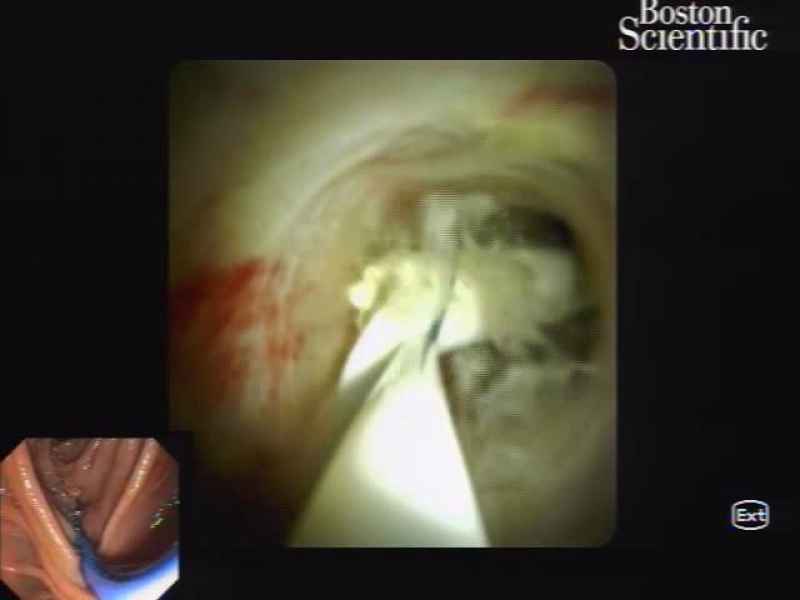

Percutaneous transcystic cholangioscopy-guided electrohydraulic lithotripsy in a patient with altered surgical anatomy - 1.º Prémio (Vídeo)

Vídeos